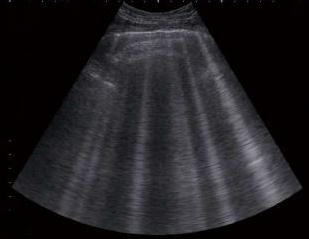

Veterinarians also use the stethoscope to listen to the dog's lungs if congestive heart failure (CHF) is suspected. One of the signs of CHF is fluid in the lungs (called edema), and that fluid tends to make crackling noises when heard with a stethoscope. Cardiologist Dr. Dave Dickson has described the sound of fluid in the lungs as "like Velcro unpeeling". However, hearing those sounds is not definitive of CHF, and other devices should be used to confirm edema, including high sleeping respiratory rates, chest x-rays, and lung ultrasound.